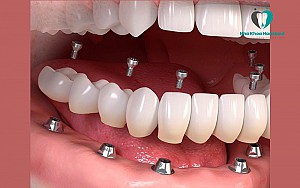

Cấy ghép Implant All On là giải pháp phục hình răng cho những bệnh nhân mất răng toàn bộ hoặc mất nhiều răng bằng cách cấy ghép một số lượng vừa đủ các Implant vào xương hàm và sử dụng chúng để tạo thành một khung, hỗ trợ tạo nên một hàm răng giả hoàn chỉnh, đầy đủ các răng.

Cụ thể hơn, bệnh nhân chỉ cần cấy ghép 4 – 6 trụ implant thay vì cấy 15 – 16 trụ vào xương hàm. Giải pháp này giúp bệnh nhân có một hàm răng chắc khỏe như răng thật, có thể ăn nhai dễ dàng kể cả với thức ăn cứng, dai…Mặt khác khiến bệnh nhân tự tin hơn khi giao tiếp từ đó nâng cao chất lượng cuộc sống.

2.3 Implant All On 4

Cấy ghép Implant All On 4 là giải pháp với kỹ thuật cấy 4 trụ Implant vào xương hàm của bệnh nhân. Tuy nhiên, để sử dụng kỹ thuật này thì xương hàm của bệnh nhân phải đủ chắc chắn và đủ dày để hỗ trợ các implant được vững chắc.